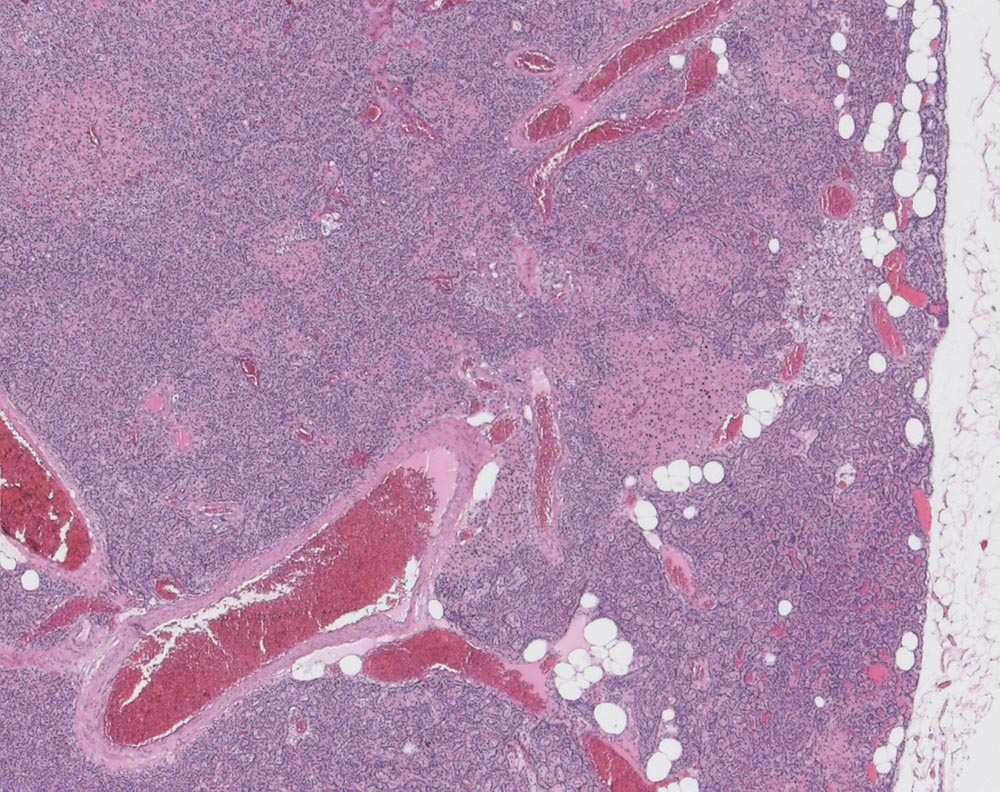

Nebenschilddrüsenadenom

Das scharf begrenzte Adenom besteht überwiegend aus Hauptzellen und Nestern onkozytärer Zellen. Nur sehr wenig Fettzellen. Reste einer atrophen Nebenschilddrüse sind nicht erkennbar.

Primärer Hyperparathyreoidismus.

Rein histologisch ist der Befund nicht von einer Nebenschilddrüsenhyperplasie abgrenzbar. Nur zusammen mit der klinischen Angabe einer einzelnen vergrösserten Nebenschilddrüse und eines primären Hyperparathyreoidisimus lässt sich die Diagnose eines Nebenschilddrüsenadenoms stellen.